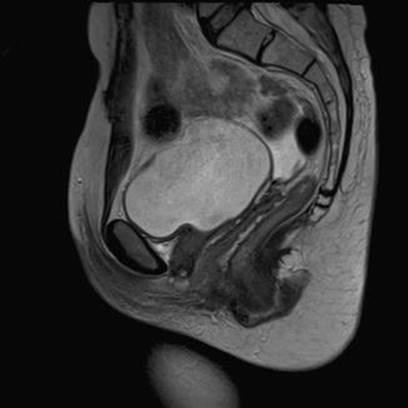

Bladder

Intraoperative bladder injury may occur during dissection of a large UD extending proximal to the bladder neck and under the bladder (Fig. 13.2), or alternatively, may occur with passage of a ligature carrier through the retropubic space if placing a pubovaginal sling.

Fig. 13.2

Urethral diverticulum extending below trigone

Injury to the bladder during UD excision is diagnosed intraoperatively by careful endoscopic examination of the bladder and bladder neck with a 70° lens following UD dissection and/or passage of the ligature carrier. The bladder should be filled and then examined to ensure that a small injury does not go unrecognized in a fold of the bladder wall.